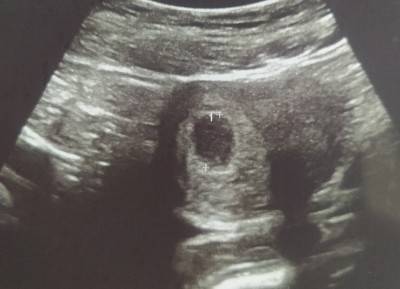

6 haftalık gebeyim ilk kez ultrasonla kese gördük doktorum küçük bir kabartida var boş değil gibi haftaya tekrar bakalım dedi. Sağ altta küçük bir nokta görüyorum sanki bakar mısınız anlayanlar 6 haftalık için normal mi

Gebelik haftası 6 haftalık